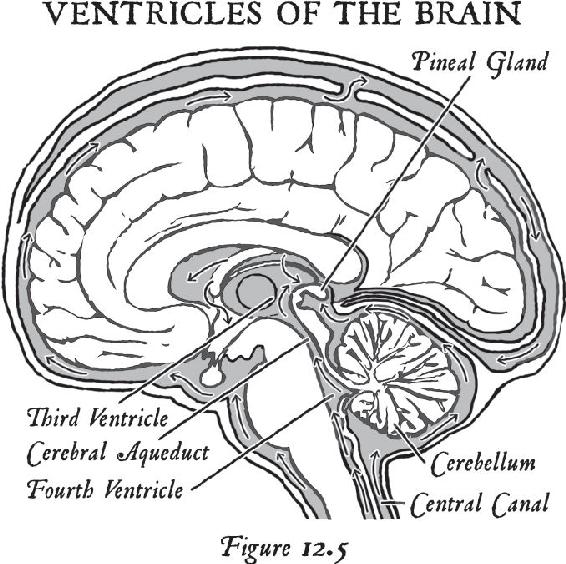

Once you are beyond your associations to this material world and you are in the unified field—chock-full of infinite possibilities—biological systems exist for taking that energy that’s beyond the vibration of matter and turning it into imagery in the brain. That’s where the pineal gland comes in, the subject of Chapter 12. Think of your pineal gland—a tiny gland perched in the central back area of your brain—as an antenna that can transduce frequencies and information and turn them into vivid imagery. When you activate your pineal gland, you are going to have a full-on sensory experience without your senses. That internal event will be more real to you in your mind while your eyes were closed than any past external experience you’ve ever had. In other words, in order to lose yourself fully in the inward experience, it has to be so real that you are there. When this happens, this little gland transmutes melatonin into some very powerful metabolites that cause you to have that type of experience. We will study the properties of this gland and then you will learn how to activate it.